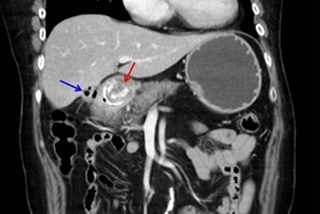

(優活健康網記者徐平/綜合報導)出現腹部疼痛症狀別輕忽,醫師提醒兇手極有可能是膽結石!一名約35歲李姓女子,因為上腹疼痛,嘴唇發白到冒冷汗,到肝膽腸胃科求診。抽血檢查發現患者肝指數高升,GPT超過500 IU/L(正常值為7~35 IU/L),醫師透過腹部超音波檢查發現原來患者是因為膽結石引起急性肝炎及急性膽囊炎。醫師提醒,若膽結石阻塞在膽囊出口或膽道,可能會引起膽囊炎、膽道炎或併發急性肝炎等肝功能異常,不可不慎。膽結石發生率逐年增加、年輕化南投醫肝膽腸胃科醫師洪弘昌表示,根據期刊研究,膽結石發生率有逐年增加傾向,年齡亦有年輕化的趨勢。肝膽關係密切,肝臟製造分泌膽汁,經膽管送至膽囊暫時儲存,再送至十二指腸吸收消化。大多數初期或較小顆的膽結石患者沒有明顯的症狀,而一旦開始出現不適的症狀,患者多半有右上腹疼痛、上腹部飽脹感或悶痛感、時而打嗝噁心嘔吐等症狀,甚至進一步疼痛到後背或後肩,這種突然的劇痛往往令患者無法忍受,緊急至急診就醫緩解和接受進一步治療。膽囊切除後要以清淡飲食為主南投醫院外科主任李博彰表示,運用腹腔鏡進行膽囊微創切除手術,相對於傳統手術具有較低的死亡率,可縮短住院時間、減少組織傷害。膽囊切除並不會影響身體主要維生系統的運作,傷口癒合後,日常行動及作息如同一般人,並不會有太大差異。但由於膽汁主要消化油脂類的食物,所以膽囊切除後的飲食必須以清淡為主。建議採取低油脂、低膽固醇的飲食,民眾可進一步諮詢醫師及營養師,依據每個人的身體狀況,獲得量身訂做的實用指南。